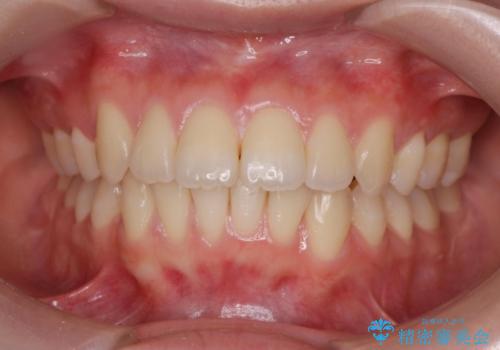

マウスピース矯正が煩わしい ワイヤー装置での非抜歯矯正

担当医 藤巻太一朗